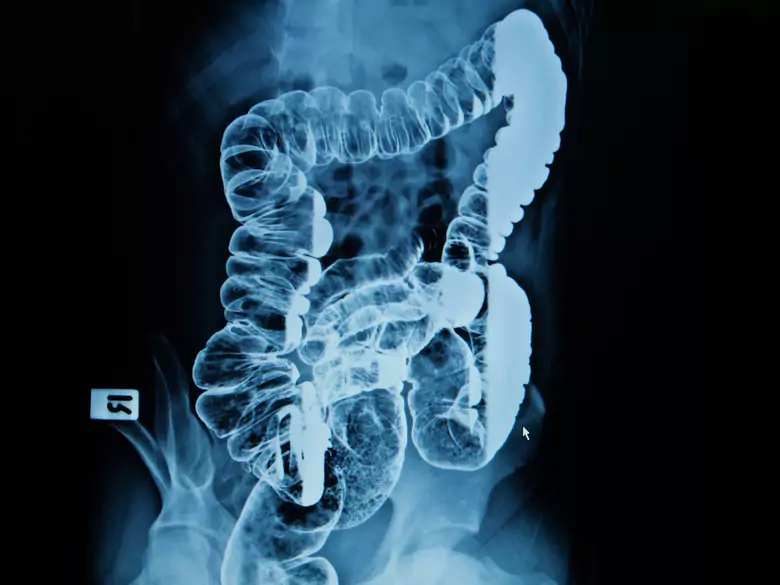

Intestinale Angiodysplasie - Ursachen, Symptome, Diagnose, Behandlung

Intestines

Symptomen und ablauf intestinale Angiodysplasie